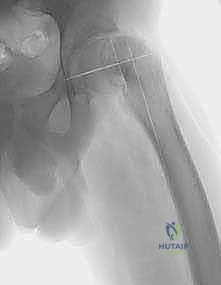

الخطوة الثانية: وضع الأسلاك الدليلية (Guide Wires)

تحت توجيه الأشعة السينية المستمرة داخل غرفة العمليات (Fluoroscopy)، يقوم الدكتور هطيف بإدخال أسلاك دليلية بالزوايا الدقيقة التي تم حسابها مسبقاً في مرحلة التخطيط. هذه الأسلاك تحدد مسار القطع العظمي ومسار الشريحة المعدنية التي ستُستخدم للتثبيت.

الخطوة الخامسة: التثبيت الصلب (Rigid Fixation)

للحفاظ على هذا الوضع الجديد حتى يلتئم العظم، يتم استخدام شرائح ومسامير معدنية قوية جداً. قديماً كانت تُستخدم الشريحة ذات الشفرة (Blade Plate)، ولكن اليوم، يستخدم الأستاذ الدكتور محمد هطيف أحدث أنظمة التثبيت العالمية مثل (Dynamic Hip Screw - DHS) أو الشرائح التشريحية المغلقة (Locking Plates) التي توفر ثباتاً مطلقاً وتسمح بالتئام أسرع.